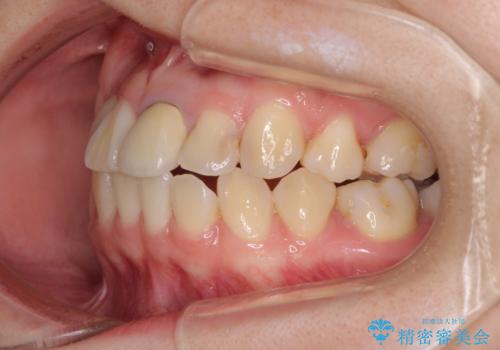

- 奥歯が痛いとのことで来院された患者様です。

上顎親知らず周辺の炎症と、神経組織の失活した歯の炎症による痛みが認められたため、親知らずの抜歯と根管治療を行いました。

根管治療を行った歯はクラウンによる補綴治療が必要となりますが、高校生の頃に行った矯正治療の後戻りも気になるとのことで、補綴治療を行う前に矯正治療を行うこととしました。

後戻りは軽度であり、インビザラインにて歯列を整え、その後にオールセラミッククラウンにて補綴治療を行うこととしました。